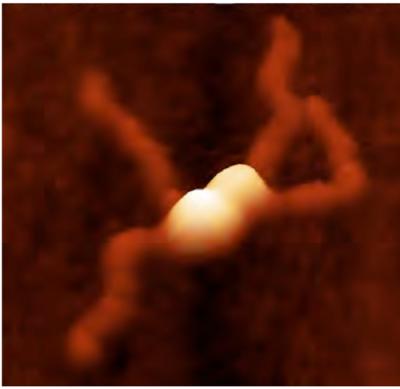

RepA naturally sticks together in pairs. When a pair of RepA proteins bumps into another pair, as when the cell is starting to get crowded with plasmids, the two pairs of RepA preferentially stick to each other. They form a complex back-to-back, with both having their DNA-grabbing parts facing outward.

When RepA forms this four-part molecule, the plasmids are said to be 'handcuffed,' because two rings of DNA are captured with the locked-up and non-functional RepA complex in the middle.

Once it is handcuffed like this, the plasmid will no longer replicate. Schumacher said this mechanism is apparently how RepA prevents the plasmids from overpopulating the bacterial cell.